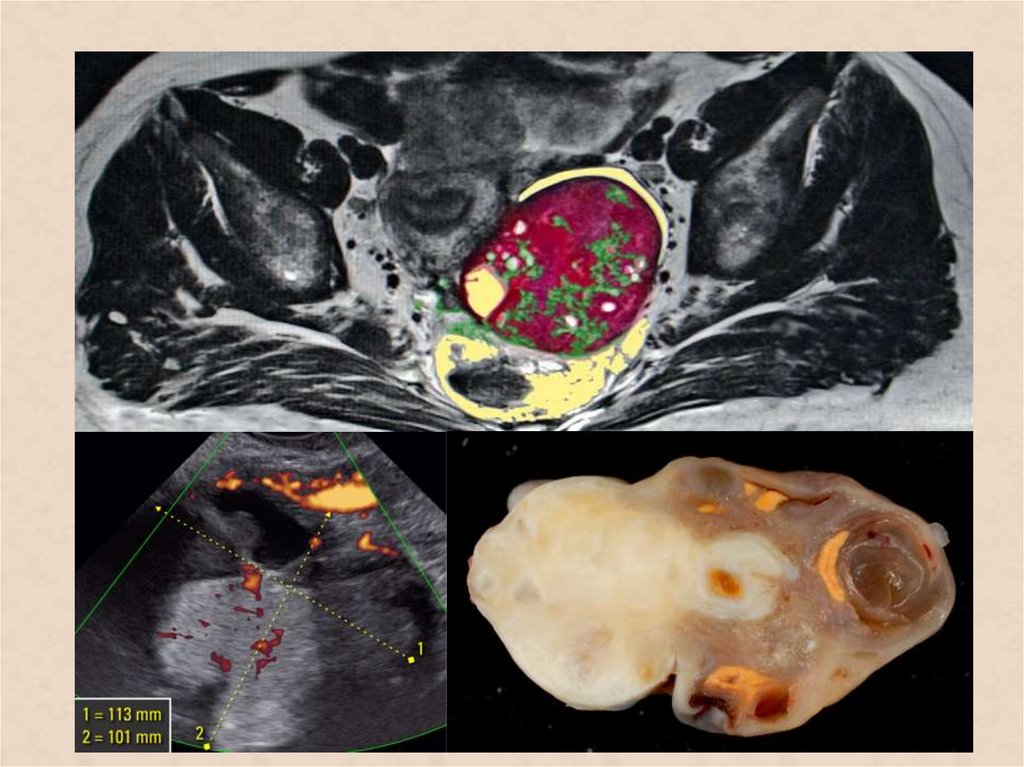

• Гинекологическое исследование (ректовагинальное

исследование);

• Методы визуализации (УЗИ, МРТ, КТ малого таза);